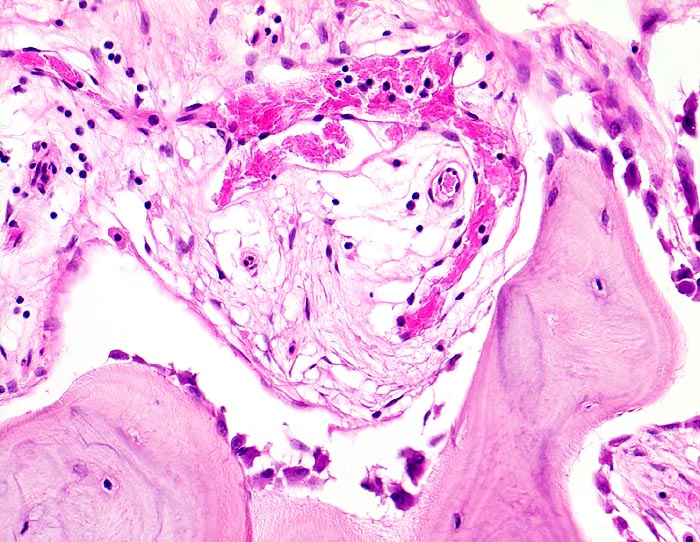

Zone mit gesteigertem Knochenanbau. Das Spongiosabälkchen ist von einer Osteoblastentapete bedeckt, welche neuen Knochen anbauen. Das Mark zeigt eine lockere Fibrose mit vermehrten kapillären Gefässen.

Die Patientin hatte wiederholt über Knieschmerzen geklagt. Autoptisch zeigte das Kniegelenk eine leichte Arthrose. Aus der auffallend verdickten Tibia wurde eine Gewebsprobe zur Untersuchung entnommen.